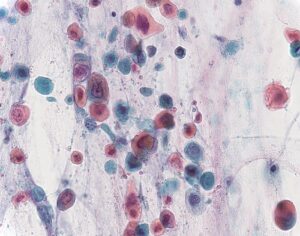

Non-small cell lung carcinoma

Diventa possibile, grazie a una nuova scoperta del Queen Alexandra Hospital di Portsmouth (Gran Bretagna), prevedere l’esito del trattamento del cancro ai polmoni. Test genetici hanno rivelato infatti che alcuni geni responsabili della sensibilita’ ai farmaci sono associati alla sensibilita’ chimica effettiva del cancro al polmone di tipo NSCLC (Non-small cell lung carcinoma) a determinate sostanze. “Non abbiamo scoperto una correlazione diretta tra l’espressione di un solo gene con le reazioni del tumore a una sostanza, ma questa correlazione era presente invece in gruppi specifici di geni”, ha spiegato Ian Cree, primo autore dello studio pubblicato sulla rivista BMC Cancer. “Siamo riusciti quindi a scoprire dei ‘complessi’ genetici, associati a combinazioni di sostanze chimiche, che permettono di prevedere in partenza la sensibilita’ al trattamento”, ha detto Cree. “In questo modo, sara’ possibile elaborare delle chemioterapie personalizzate per ogni paziente“.